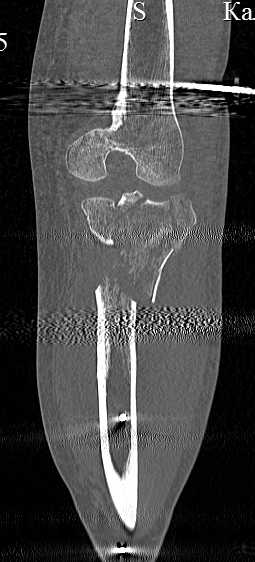

Серия КТ сканов в аппарате